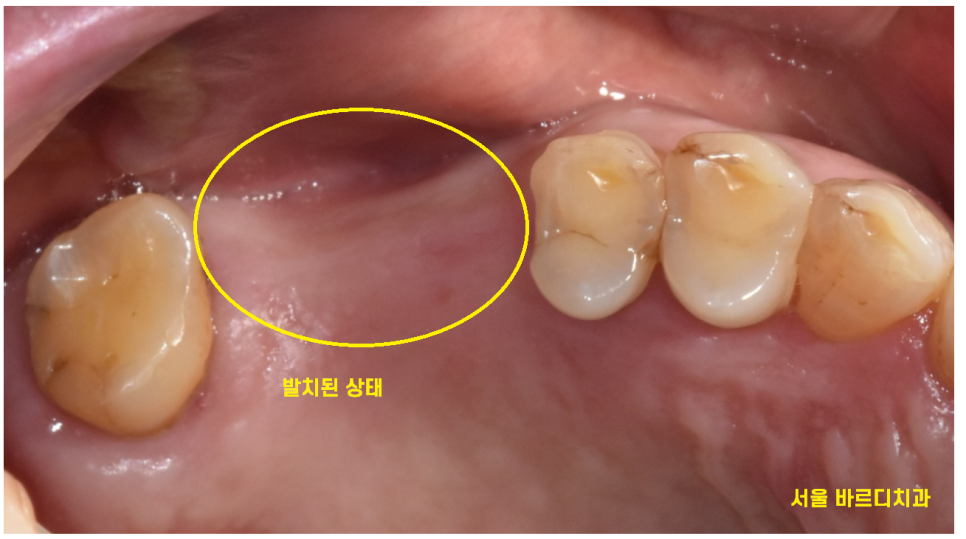

문제가 있어보이는 치아 2개

너무 아파서 발치를 원하셨습니다.

강일동 치과에서는 환자분이 멀리서 오셨기에

발치 후 당일 임플란트 수술을 진행해드릴 수 있다

설명드렸는데요.

문제 치아를 뽑고

발치 후 당일 임플란트 수술 완료해드렸습니다.